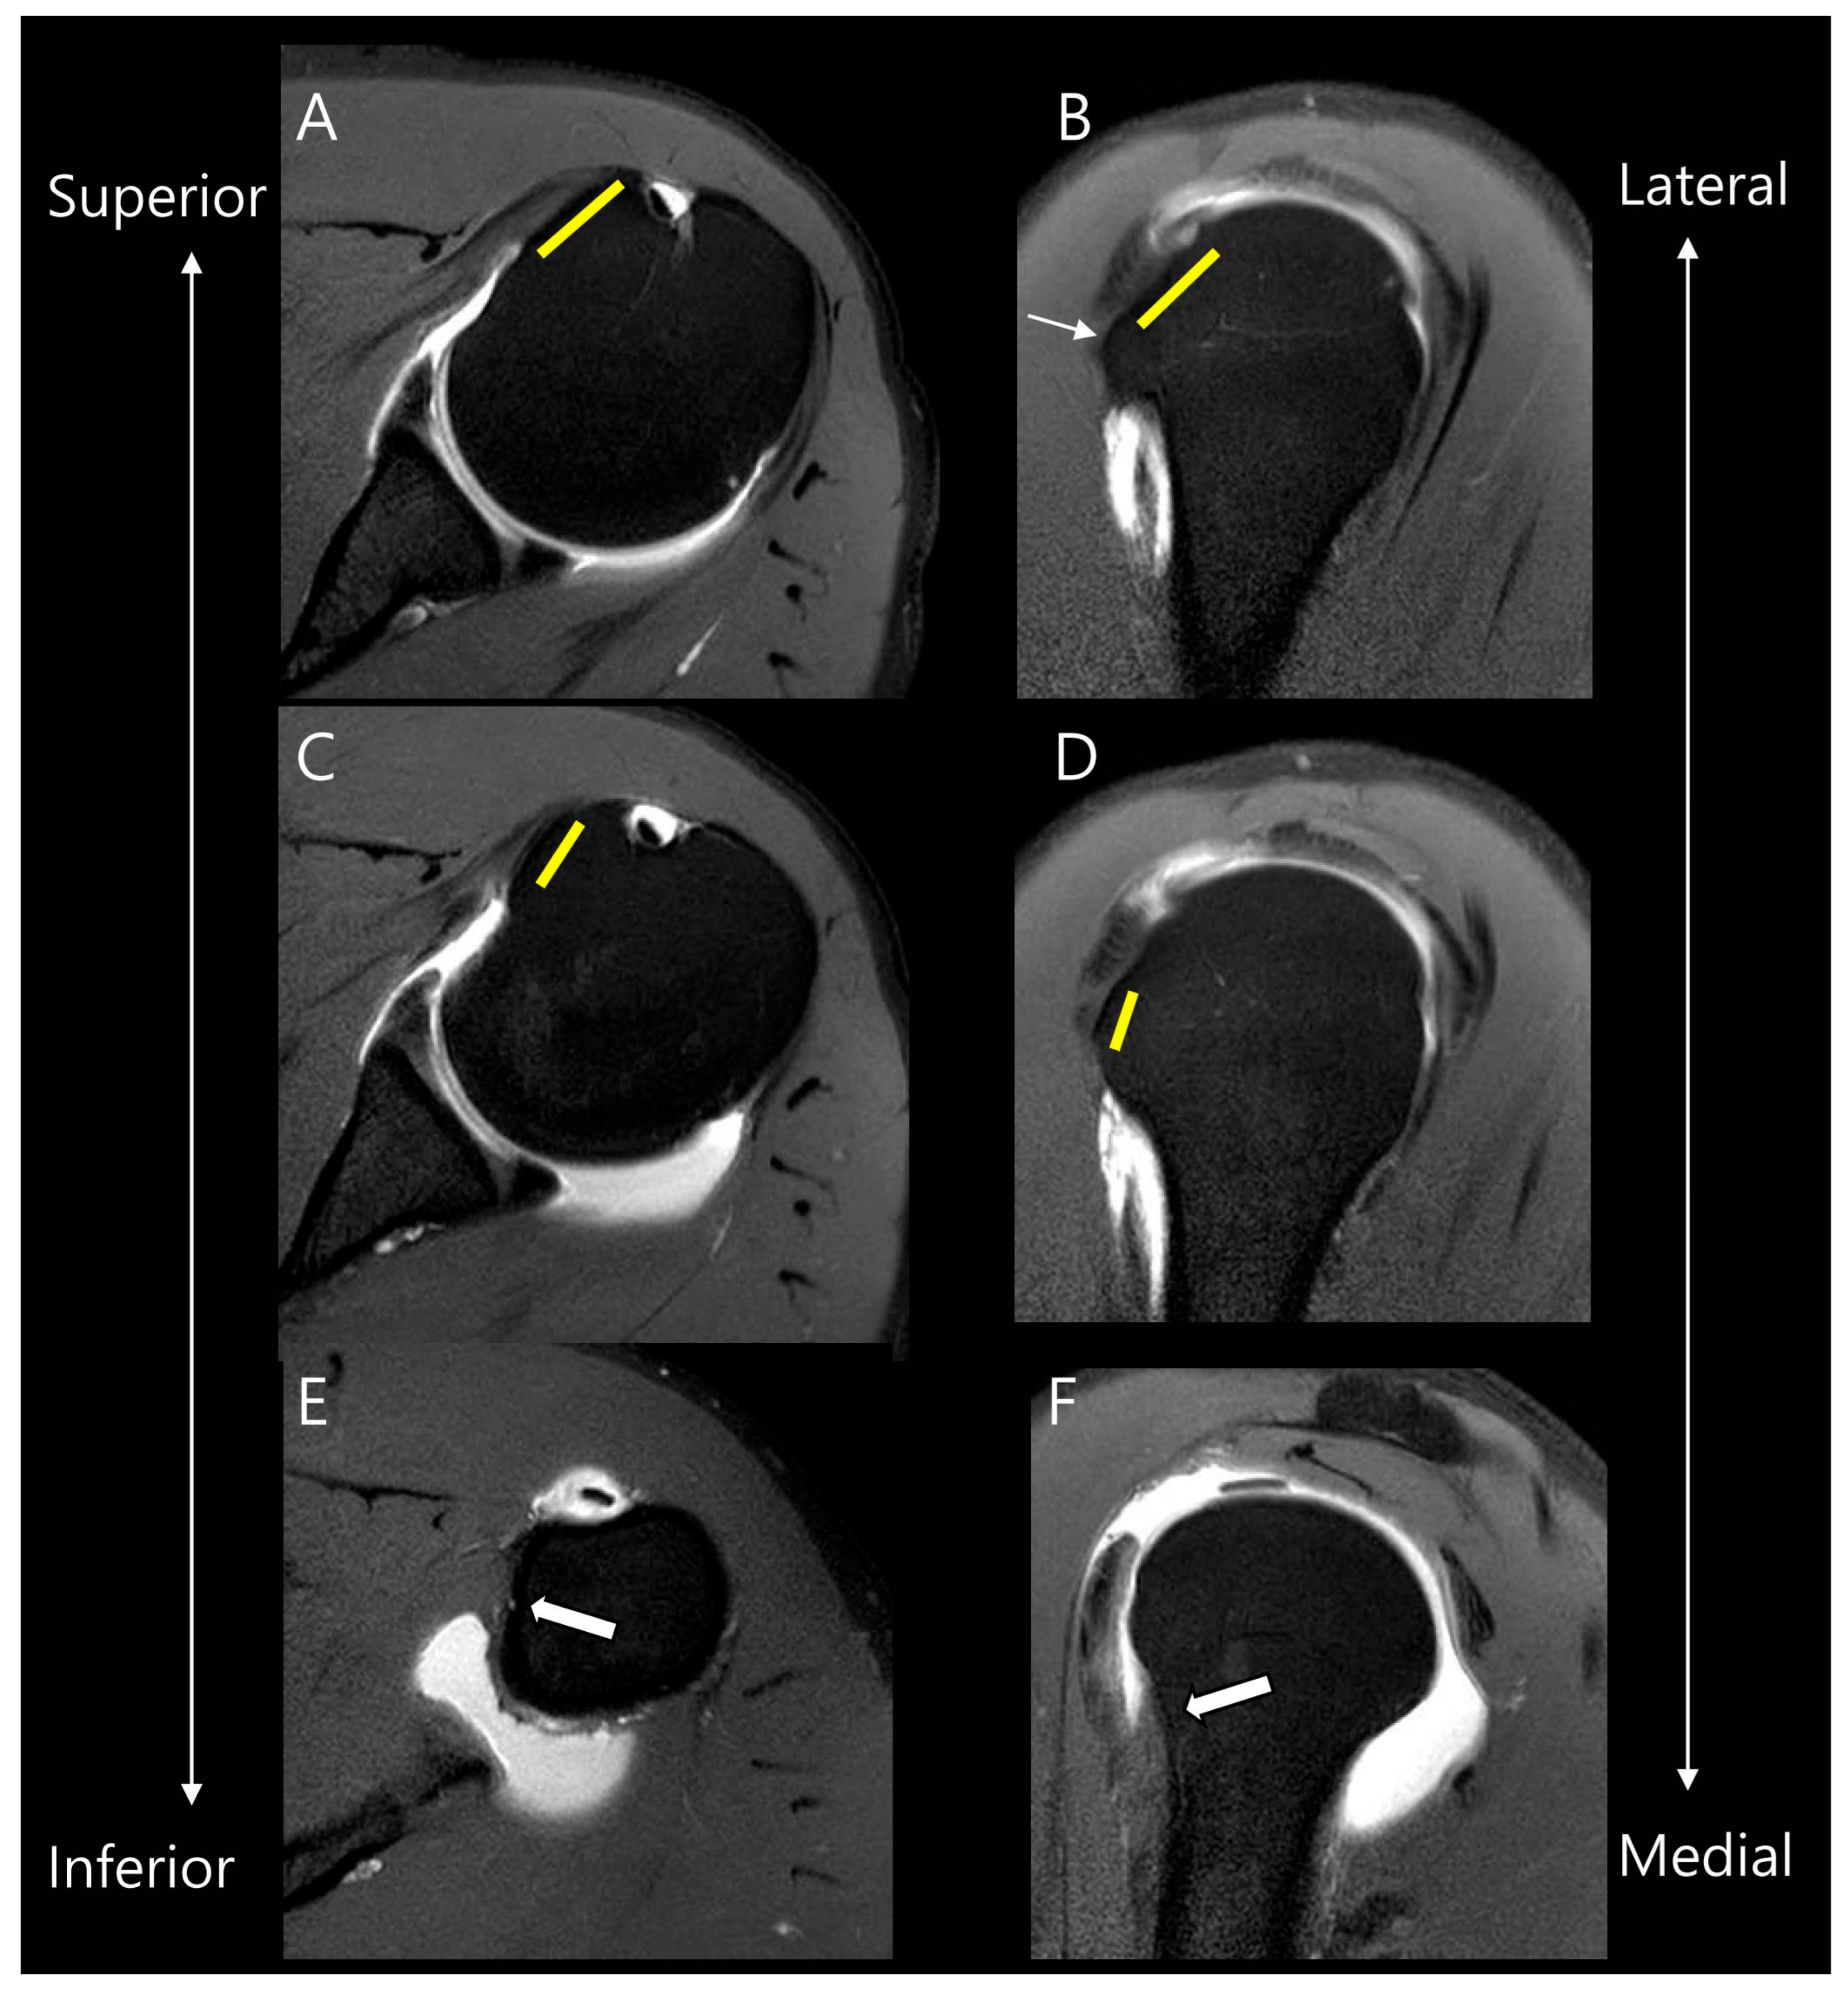

Before evaluating the SSC tear, we reviewed the anatomy according to the four facet theory of the SSC footprint as described in the Yoo and Rhee classification [8]. In this theory, the first two facets represent 60% of the total footprint, corresponding to the tendinous portion of SSC attachment. The first facet corresponds to the upper one-third of the SSC footprint as described by Lafosse [8]. On axial images, it appears relatively wide and flat, while on sagittal images, it demonstrates a horizontal orientation [9]. Anatomically, the first facet is positioned most superiorly and laterally. The second facet corresponds to the upper two-thirds of the SSC footprint according to Lafosse. On axial images, it appears relatively narrow, and on sagittal images, it is oriented more vertically [9]. It is separated from the first facet by a bony ridge and is located more inferiorly and medially relative to the first facet. In comparison, the following third and fourth facets represent the large muscular insertion of the SSC, which aligns with the caudal one-third described in the Lafosse classification [8]. Figure 2 presents an illustration correlating the facet theory with actual MR images.

Figure 2.

Anatomy of facets of the subscapularis tendon on MR images. On oblique axial and oblique sagittal MR images, the first facet (yellow lines in (A,B)) is located more superiorly and laterally compared to the second facet (yellow lines in (C,D)). They are separated by a bony ridge (thin arrow in (B)). The following third and fourth facets represent the large muscular insertion in the inferior attachment (thick arrows in (E,F)).